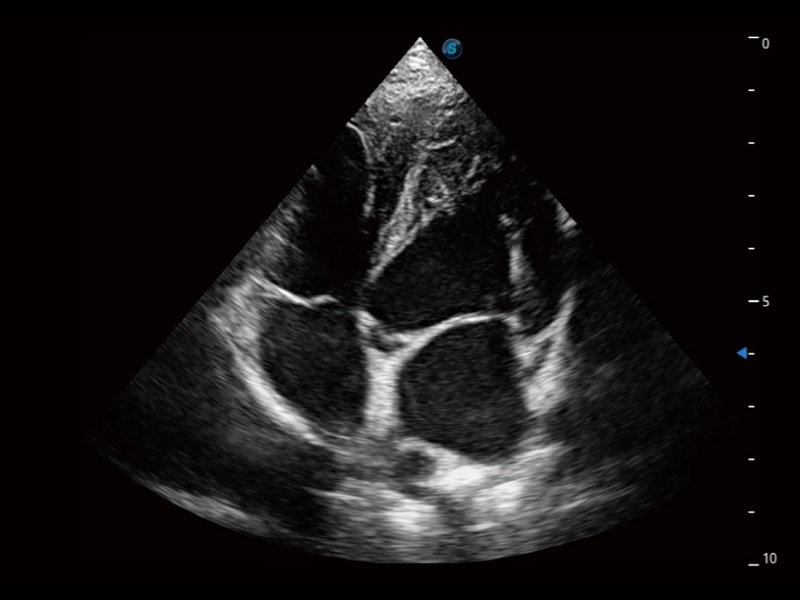

优异的基础图像

ProPet 70 全新的动物超声智能软件和丰富的探头群,为动物医生提供了高清晰度和精细分辨率的图像,无论在宠物、马科、畜牧还是实验室动物等应用中都可以轻松应对,为您的日常工作带来满意的体验。

(犬)四腔心